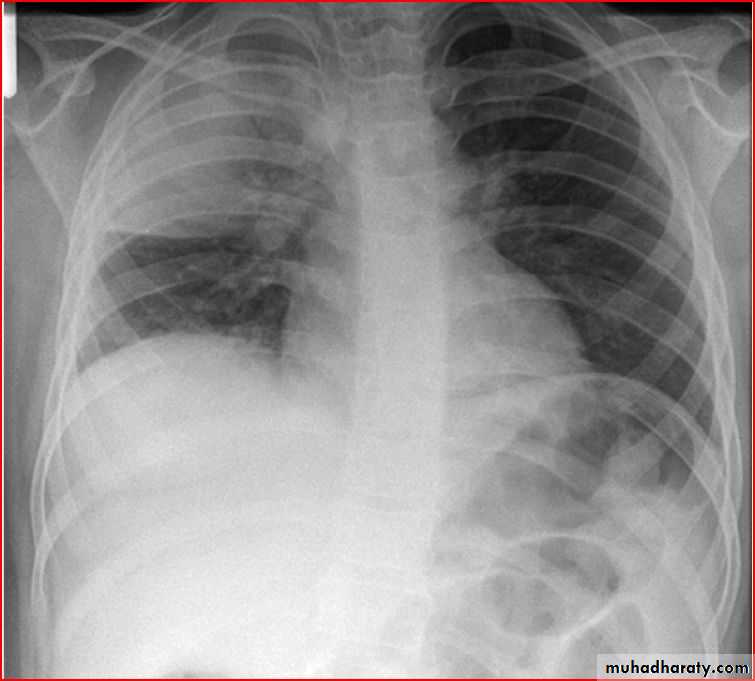

Homgenous opacity filling the rt. Hemithorax there is shefting in trachea to rt. Side mean this is collapse